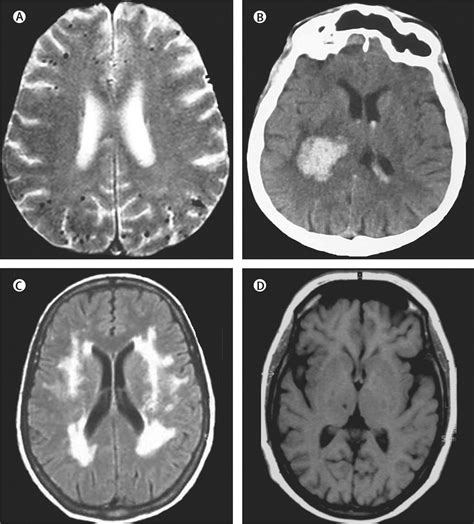

• Imaging Studies: Such as ultrasound, MRI, or CT scans to visualize the blood vessels and assess their condition.